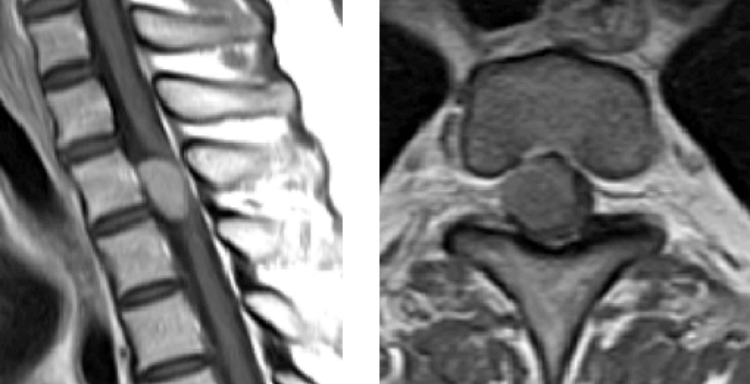

脊髄腫瘍

脊髄に発生する腫瘍の摘出術を行っています。手足に麻痺を残さないために、手術用顕微鏡の使用と、術中モニタリングを行うことにより、難易度の高い症例でも良好な成績を得ています。